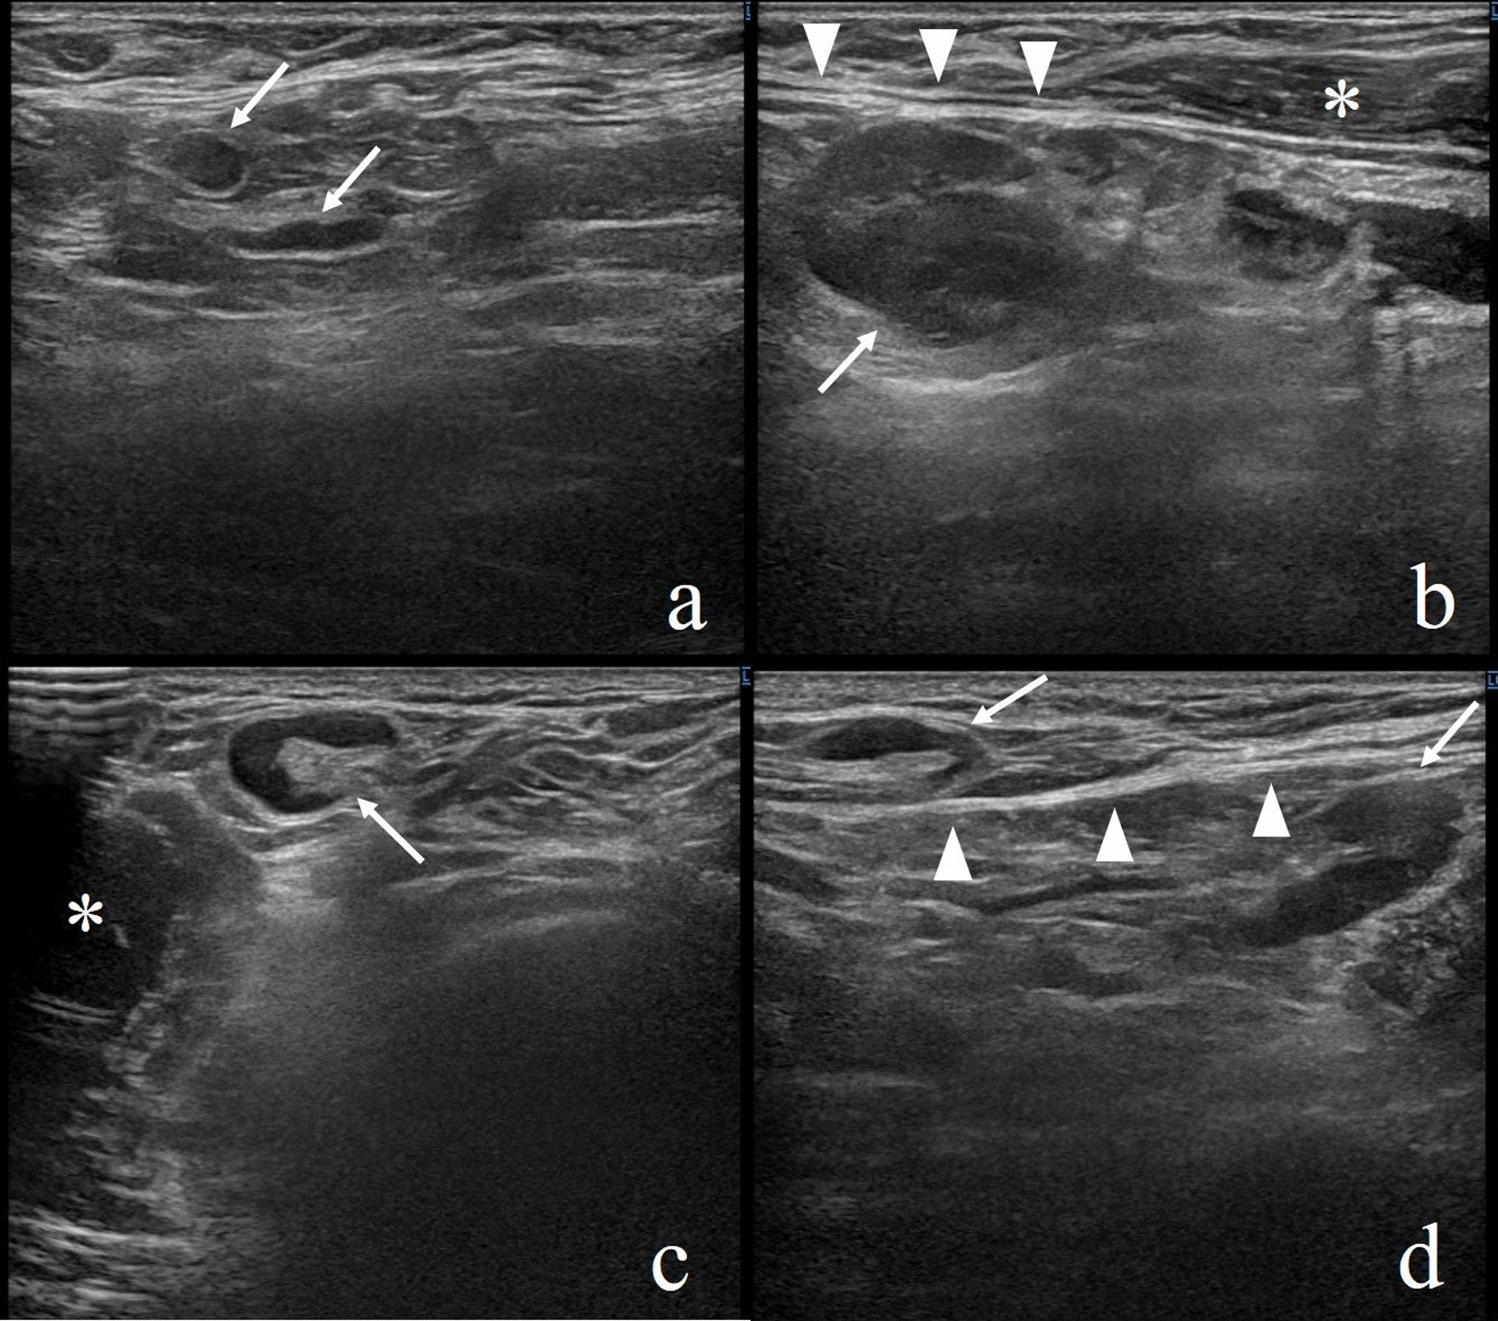

We present a case of axillary lymphadenopathy that occurred after COVID-19 vaccination and that mimicked metastasis in a Japanese woman in her 30 s. There was no lymphadenopathy on her ultrasonography (LOGIQ E10s, GE healthcare Japan, Tokyo, Japan) for breast cancer screening performed on the same day as the administration of the Pfizer-BioNTech vaccine (Fig. 1a). This was the first time she had been vaccinated against COVID-19. Nine days later, she noticed painful axillary masses and we found lymphadenopathy in her axilla on ultrasonography. The largest of her swollen lymph nodes was deep in level I, and the size was 20 × 15 mm (Fig. 1b). The lymph nodes at the superficial axilla were up to 12 × 7 mm (Fig. 1c). In a follow-up ultrasonography 14 days after the vaccination, the lymph nodes shrank slightly (Fig. 1d), and we determined their swelling to be reactive.

Fig. 1

A woman in her 30 s with no medical antecedents. a The normal axillary lymph nodes on screening ultrasonography (arrows). b Nine days later, targeted sonography revealed a left axillary lymph node measuring 20 × 15 mm (arrow) deeper than the lower edge of the pectoralis major muscle. c Lymph nodes up to 12 × 7 mm were found on the front side of the lower edge of the pectoralis major muscle (arrow). d In a follow-up ultrasonography 14 days after vaccination, the lymph nodes shrank slightly (arrows). Arrowheads, the hyperechoic line of the lower edge of the pectoralis major muscle; *the pectoralis major muscle